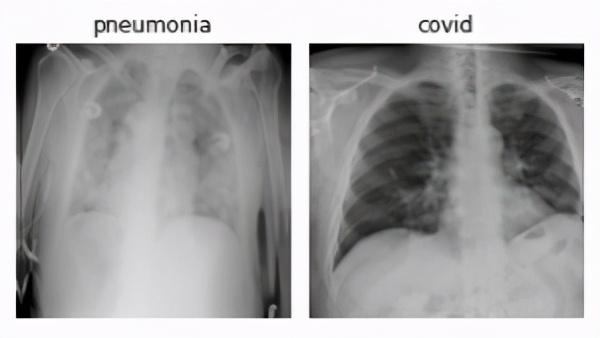

很长一段时间以来,计算机支持的医学图像被用于诊断,如CT扫描、X射线等。此外,计算机视觉技术的最新发展使医生能够通过将图像转换为三维交互式模型来更好地理解这些图像,并使其更易于解释。

如果我们看一下计算机视觉的最新使用案例,那么我们会发现它是在用胸部x光检查COVID-19病例。此外,根据武汉市放射科的一项研究,深度学习方法可以有效地区分Covid-19和社区获得性肺炎。

检查一下由Kaggle提供的COVID-19胸部x光数据集,并在实施过程中自己动手。

COVID-19胸部x光数据集:https://www.kaggle.com/bachrr/covid-chest-xray